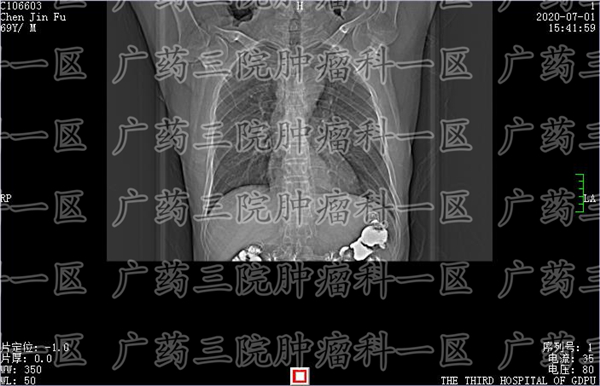

广药三院肿瘤科一区就有一个病人,因为吞咽不适到医院进行胃镜检查,在距离门齿25-28cm后壁见一不规则溃疡,表面凹凸不平,触之易出血,质中,局部管腔变窄;胃体,大弯侧散在条索状糜烂;胃窦,蠕动正常,黏膜潮红,四壁散在点片状糜烂。当地医生考虑后认为,可能是食道CA或黏膜慢性炎,伴活动性炎及坏死。

而想要明确到底是食管黏膜慢性炎症or食管癌,医生认为还是要看金标准——病理活检。通过病理活检,如果确实是癌症,那么就要尽快进行对应的综合治疗。广药三院肿瘤科一区,医生会为食管癌病人进行活检,明确病理类型后,根据癌肿瘤的特性,选择适当的微创技术制定治疗方案。